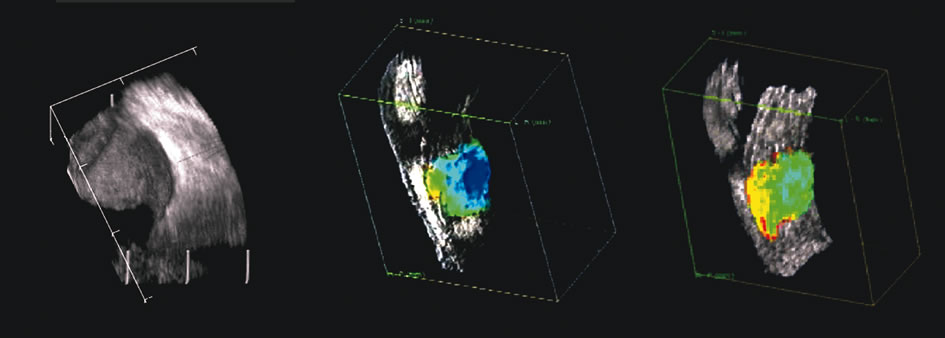

The use of three-dimensional data acquisition along with surface and volume rendering of three-dimensional ultrasound data is becoming more commonplace in medical ultrasonography,37 particularly in obstetrics and gynecologic applications.38–40 In ophthalmology, instrumentation that digitizes radial B-scans is commercially available.41,42 In addition, tissue volume measurements made from delineation of tissue boundaries in serial scans have been shown to have an accuracy of ±2% in vitro.43 Such measurements must be corrected for the anamorphism inherent in B-scan images, where anterior-to-posterior scale is related to the speed of sound and lateral scaling is related to transducer angle or displacement. Comparison of in vivo volume determinations of ocular tumors made with this method and volumes computed from ultrasonically determined tumor linear dimensions using an ellipsoidal solid formula44 showed the latter to be of variable accuracy, sometimes producing errors of up to 50%.

The representation of volume and three-dimensional perspectives of the diseased vitreous, retinal detachment, choroidal detachment, and tumors can add to presurgical conceptualization and is critical to characterization of tumors in relation to prediction of lethality.45 In addition, volume measurement of the choroid permits studies of both surgical and physiologic rates of clearance of hemorrhage, whereas vitreous volume studies can make the estimation of gas or other vitreous substitutes for replacement more accurate (Fig. 25).

Fig. 25. A 3D reconstruction of serial scans of a posterior pole melanoma taken with a 10 MHz transducer (left) shows the extent and relative asymmetry of the tumor within the vitreous cavity. 3D biometry can be useful for treatment planning for radiotherapy and brachytherapy. 3D reconstructions of 50 MHz serial ultrasound scans and parameter images of a melanoma involving the ciliary body and anterior uvea (center, right) before and after treatment with combined ultrasound hyperthermia and brachytherapy. Changes in the concentration of ultrasound scattering elements related to tissue necrosis are seen as color scale in the pre- and postimage region of the tumor shifts, from blue, indicating relatively low acoustic concentration, to yellow and green, indicating higher concentrations of scatterers.